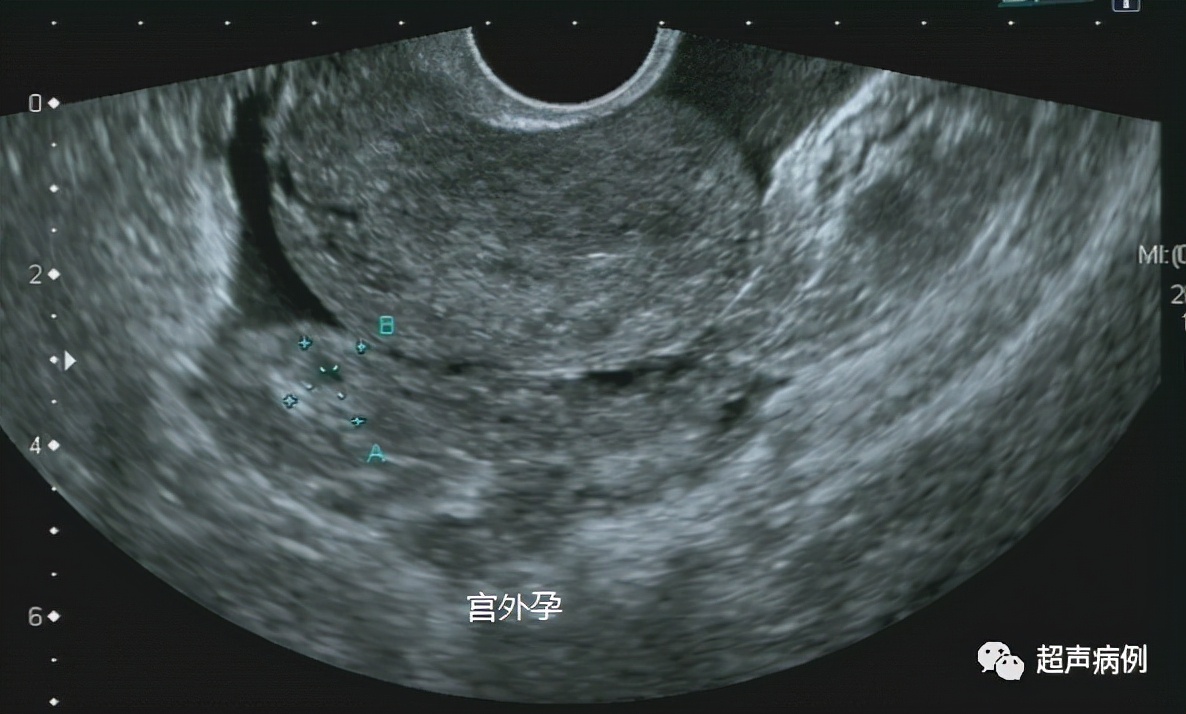

4、明确诊断早期妊娠(经腹无法观察的早孕);

5、排除有无宫外孕等情况。